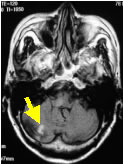

小脳梗塞